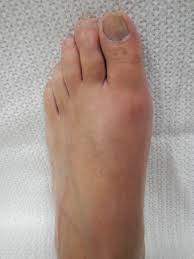

통풍은 주로 급격한 발작적인 증상을 보이며, 이는 주로 관절 부위에서 발생합니다. 통풍 발작의 주요 증상은 다음과 같습니다:

- 극심한 통증: 통풍 발작은 강한 통증을 동반합니다. 통증은 일반적으로 밤이나 새벽에 시작하여 관절 부위에 급격히 나타나며, 뚜렷한 통증을 유발합니다. 종종 "화살통 통증"이라고도 불리며, 통증의 강도는 매우 높을 수 있습니다.

- 부어오름과 발적: 통풍 발작 부위의 관절은 붓고 붉게 변할 수 있습니다. 특히 발가락의 발적이 흔하며, 관절 주위에 염증이 발생하는 결과입니다.

- 열감과 민감도: 통풍 발작으로 인해 발작 부위는 뜨거워지고 민감해질 수 있습니다. 심한 경우, 신체의 발열과 함께 민감도가 증가하는 것을 경험할 수 있습니다.